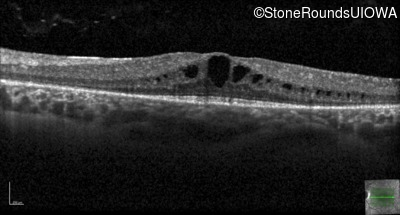

Optical Coherence Tomography - Left - 20/32

Exemplar / OCT Stack

OCT Stack